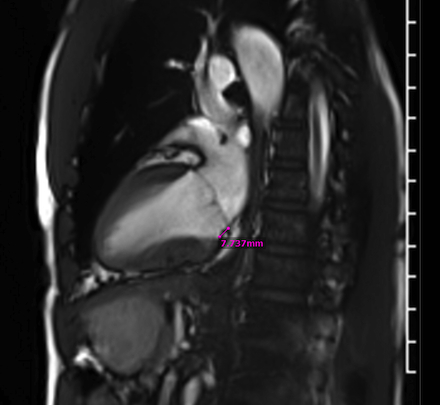

A 51-year-old African American male with history of posterior papillary muscle premature ventricular contractions (PVC), PVC induced cardiomyopathy, and family history of sudden cardiac death in his mother who presented to the emergency department due to palpitations. Electrocardiogram (ECG) showed sustained monomorphic VT at a rate of 160 bpm. This converted to normal sinus rhythm with intravenous amiodarone and metoprolol. Further work up included cardiac magnetic resonance which identified a 4 x 1.8 x 1.4 cm SMA on the basal inferior and inferolateral walls. There was near transmural late gadolinium enhancement (LGE) of the aneurysm and an associated 7 mm of MAD with posterior mitral valve prolapse (MVP). He underwent left heart catheterization which was normal. ECG showed a superior right axis with associated right bundle branch block which correlated to a basal inferolateral exit and to the location of the SMA. Ultimately the patient underwent implantation of secondary prevention implantable cardioverter-defibrillator and initiation of sotalol.